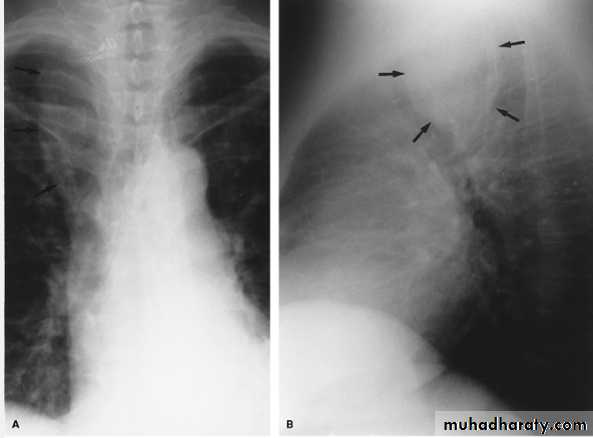

Pneumomediastinum.

Vertical dark (lucent) lines representing air within the mediastinum are usually seen at or above the level of the aortic arch.

On the posteroanterior view (A), these can be seen extending up into the lower cervical soft tissues (arrows).

On the lateral view (B), dark linear air collections can be seen in front of and behind the trachea.

chest practice